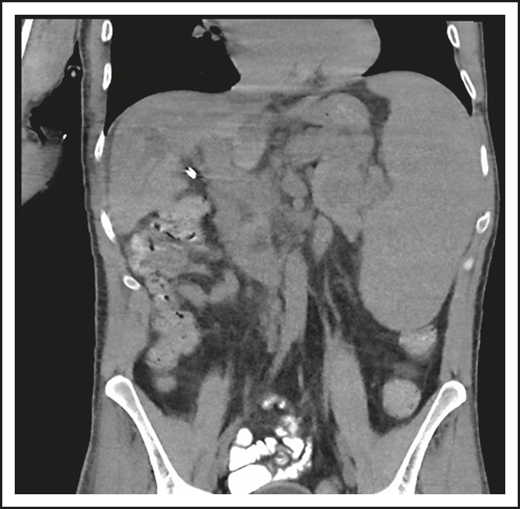

A 46-year-old male contractor who smoked but was previously healthy had acute AIHA. He was treated with prednisone and recovered. This occurred again the following year, and he required blood transfusions. Four years later, AIHA again occurred; he developed a clot in his aorta with thrombosis of his splenic artery, resulting in a splenic infarct. He had a splenectomy and recovered uneventfully. The following year, he developed pneumonia with a large posterior empyema; Streptococcus pneumoniae was cultured (Figure 1). The collection was drained, complicated by a collapsed lung, but he recovered. Six months later, he had a second bacterial pneumonia, and immunoglobulin was measured. These tests showed remarkably low levels of serum immunoglobulins: IgG, 71 mg/dL (normal range, 639-1349); IgA, 6 mg/dL (80-350); and IgM, 15 mg/dL (45-250). He had no protective titers of antibody to any vaccines. Intravenous immunoglobulin replacement was instituted, and the patient experienced no further episodes of either infection or autoimmunity.

(A) The patient in clinical case 1 with several episodes of severe autoimmune hemolytic anemia was only diagnosed with CVID after he had bacterial pneumonia and developed an empyema. (B) Lateral view shows the posterior empyema collection.

A second common reason for a patient to come to the attention of hematologists is the finding of an enlarged spleen, especially in an adult with lymphadenopathy. This was the reason in patient 2, who is now a 46-year-old male professional dog walker. At the age of 31, he was found to have an enlarged spleen together with cervical and axillary lymphadenopathy. Hematology was consulted, and the lymph node was biopsied; pathology revealed that he had noncaseating granuloma. He was then referred to pulmonology and, with this evidence, was diagnosed with sarcoidosis and treated with steroids for some months, but he stopped the treatment. Although he had no obvious respiratory symptoms over the following 15 years, he had a slow decline in lung function, and chest computed tomography showed hilar lymphadenopathy, ground-glass opacities with nodules, and bronchiectatic changes (Figure 2). In 2018, he had acute bacterial pneumonia, became concerned, and found on the internet that granulomata in the lungs and an enlarged spleen might be related to low serum immunoglobulin levels. He asked that this be tested; when this test was performed, he had striking low serum immunoglobulins: IgG, 97 mg/dL; IgA, <5 mg/dL; IgM, 27 mg/dL. However, within the month, he was hospitalized for pneumonia due to metapneumovirus. The diagnosis of CVID was finally made, and immunoglobulin treatment was started. The patient’s spleen remains large.

The patient in clinical case 2 had a slow decline in lung function due to his immune defect, but this was assumed to be due to sarcoidosis. Chest computed tomography showed ground-glass opacities with numerous nodules, hilar lymphadenopathy, and bronchiectatic changes. With granuloma on biopsy, these changes were consistent with granulomatous lymphocytic interstitial lung disease.